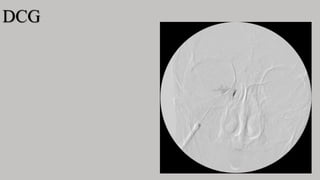

DCG

FILMS

Occipito mental –immediately following the injection to show filling and

emptying of the nasolacrimal duct

Lateral

When catheter is used

1st film-as plain film for subtraction

2nd film-when 1 ml of CM has been injected

3rd film-injection completed

The radiographs are then processed and subtracted